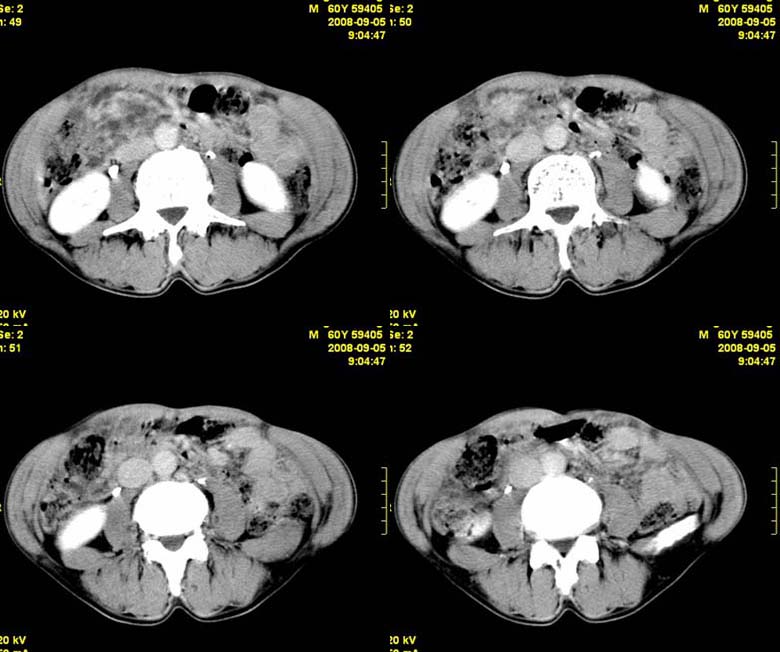

标题: CT15580:M60Y,胰腺病变,平扫+增强 [打印本页]

标题: CT15580:M60Y,胰腺病变,平扫+增强

患者,男, 60,既往有间歇腹痛病史多年,现右上腹痛,加重一月,伴右后背部疼痛,无黄疸,无发热。

考虑胰腺囊腺瘤或慢性胰腺炎

胰头区增大,胰管明显扩张,不均匀强化,且与 周围结构不清,后背疼痛,考虑为胰腺头部胰腺癌。

胰头囊腺癌

胰头囊腺癌

慢性胰腺炎

胰头囊腺癌

慢性胰腺炎并胰头癌

胰头囊腺癌。

胰腺囊腺瘤可能性大,囊腺癌不除外.

同意胰头部囊腺癌。

胰头囊腺癌可能性大。

考虑胰腺囊腺瘤或慢性胰腺炎

胰头囊腺癌

结合病史考虑慢性胰腺炎伴脓肿形成。

胰腺囊腺癌/慢性胰腺炎,建议查肿瘤标志物。

胰头囊腺瘤/囊腺癌.

胰腺炎,胰液滞留性假囊肿

考虑胰腺囊腺瘤或慢性胰腺炎。

胰头区增大,胰管明显扩张,不均匀强化,且与 周围结构不清,后背疼痛,考虑为胰腺头部胰腺癌。

胰头囊腺癌

考虑胰腺囊腺瘤或慢性胰腺炎可能性大

粘液性囊腺瘤

同意胰头部囊腺癌

胰头囊样增大不均匀强化,腺管扩张。结合病史首诊慢性胰腺炎、假性囊肿